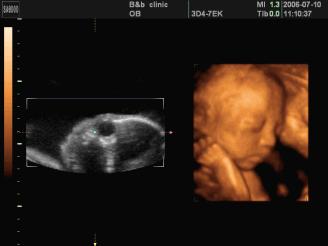

5、三维彩超:可能是土黄色,图片,静态,有排畸作用;

6、四维彩超:可能是土黄色,录像,动态,能够刻录成光盘,有排畸作用;